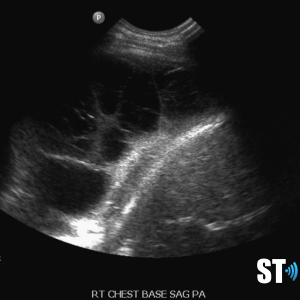

Large volume pleural effusion

Large volume echogenic pleural effusion

Large and or symptomatic pleural effusions may be treated with ultrasound guided thoracentesis which can double as a diagnostic procedure, where the fluid removed can be sent to pathology. Normal analysis of the fluid consists of cytology, chemistry and culture.

Loculated pleural effusion

complex left pleural effusion